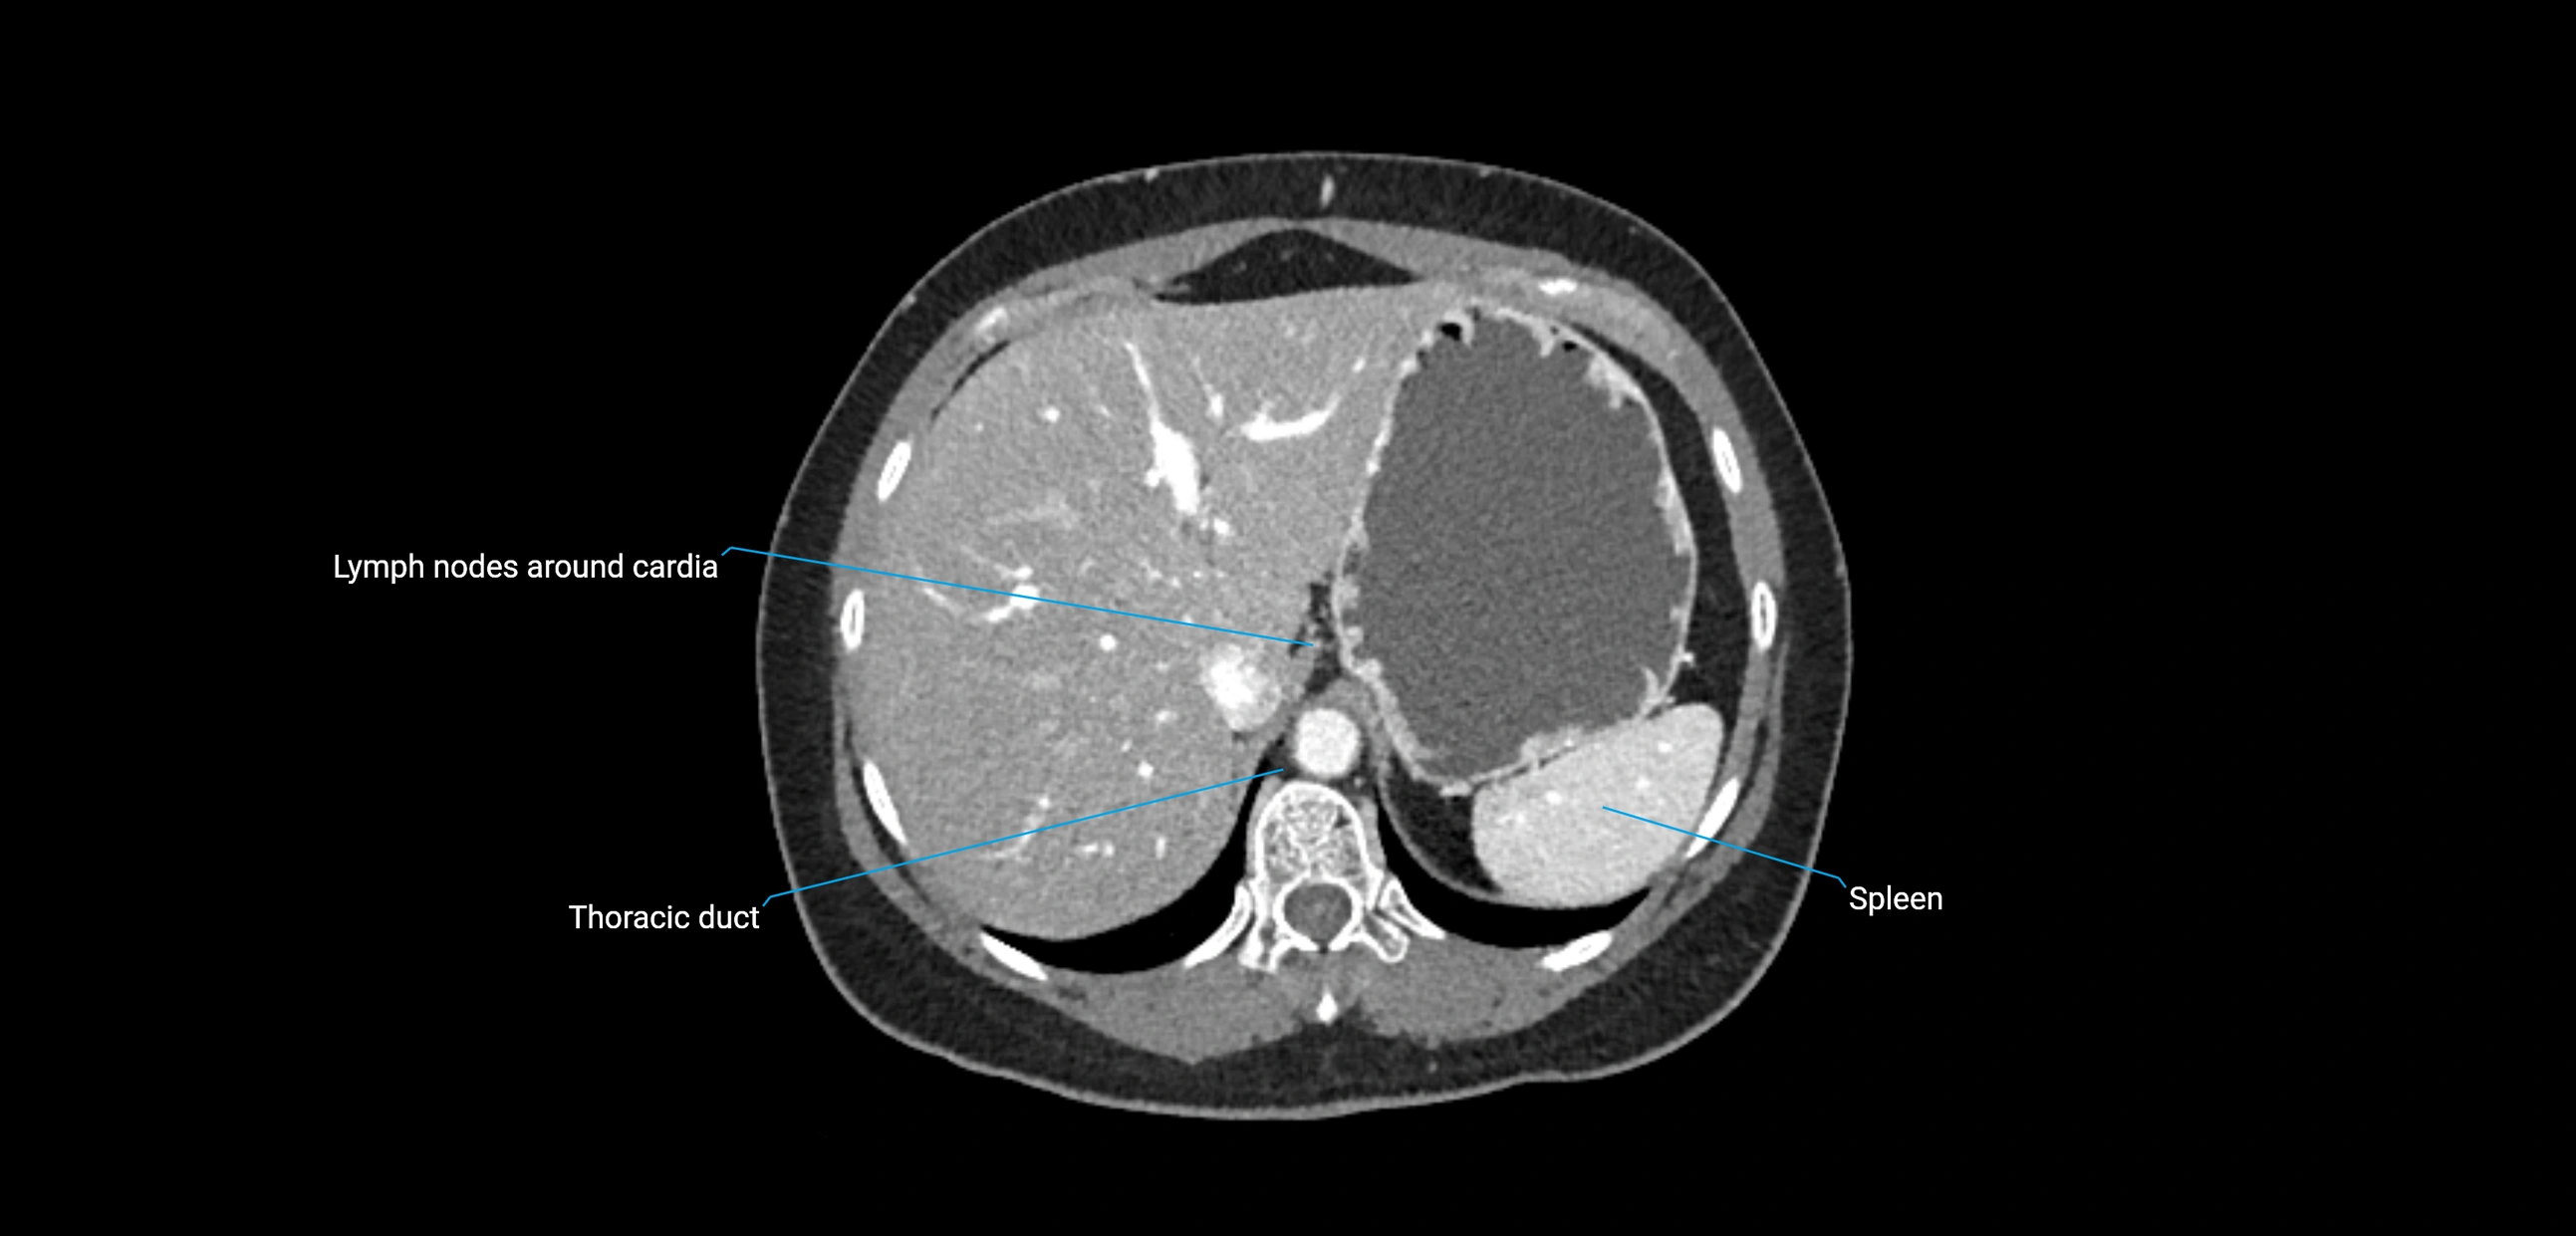

CT image

image